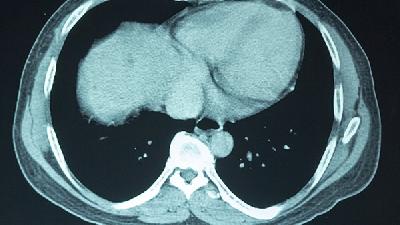

小儿脑瘫,是指小儿脑性瘫痪,一般是指出生一个月以内的婴儿由于各种原因造成的非进行性脑损伤,主要表现运动障碍和姿势异常,脑瘫患儿的表现由于病因不同而各种各样,一般由于男性抽烟,酗酒,女性多次生育或者女性患有精神疾病的情况下,出现小儿脑瘫的概率比较高,那么,脑瘫儿在孕期能查出吗,都有哪些检查方法呢?在怀孕期间,按时的做产前检查,通过对孕妇怀孕期间对胎儿的检查,可...